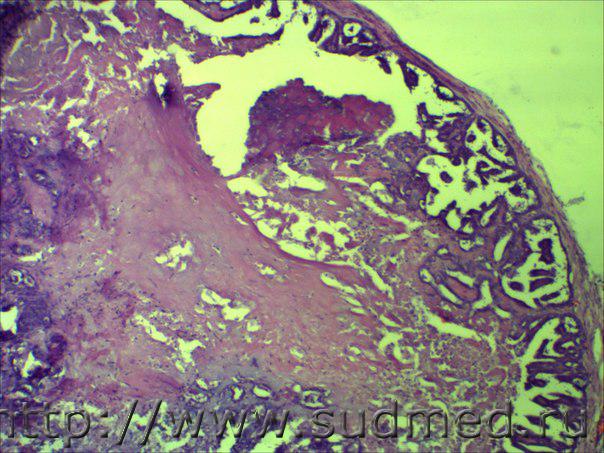

Плотное,множественное, размером с "ноготь".

Медик На фото нет чёткости,но похоже на внутрипротоковый... 31.10.2014 - 14:01

доктор морфолог Плотное,множественное, размером с "ноготь... 3.11.2014 - 07:57

наталия-верт Ув.Евгений! Процесс идет не только внутри прот... 3.11.2014 - 18:30